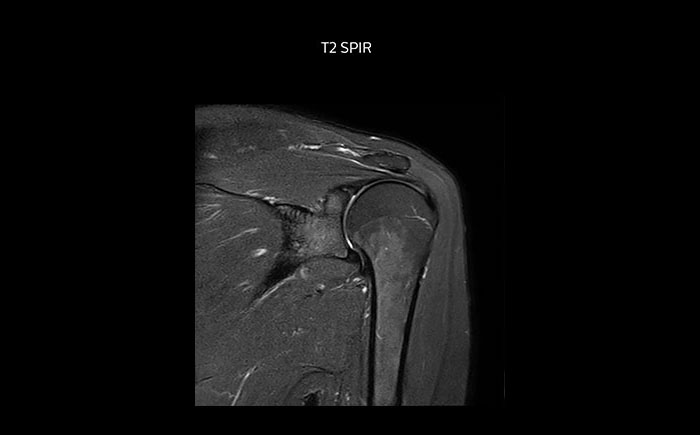

Shoulder MRI with high quality, large coverage

The Prodiva shoulder coil is very flexible and has large coverage, which makes good positioning easier, and that contributes to the superb image quality and high SNR that we get in our shoulder exams.

Scan time 2:55 min, FOV 160 mm,

acq voxels 0.55 x 0.83 x 3.0 mm.

Scan time 4:19 min, FOV 160 mm,

acq voxels 0.55 x 0.80 x 3.0 mm.

Scan time 2:50 min, FOV 160 mm,

acq voxels 0.70 x 0.99 x 3.0 mm.

Shoulder MRI with high quality, T2 SPIR

Shoulder MRI with high quality, mFFE

Shoulder MRI with high quality, STIR TSE